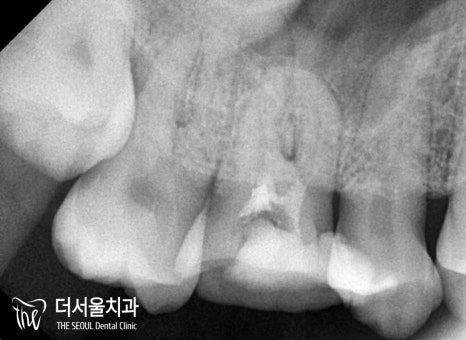

성남치과 에서는 감염된

근관 내부를 깨끗히 청소하고

빈 공간을 채워주는 과정을 거쳤습니다.

소독-충전 과정을 마친 뒤,

마치 나무 뿌리처럼

가늘고 세밀한 잔뿌리가 존재하는데요.

이런 곳들도 함께 확인하여

재발의 확률을 줄여줘야 됩니다!